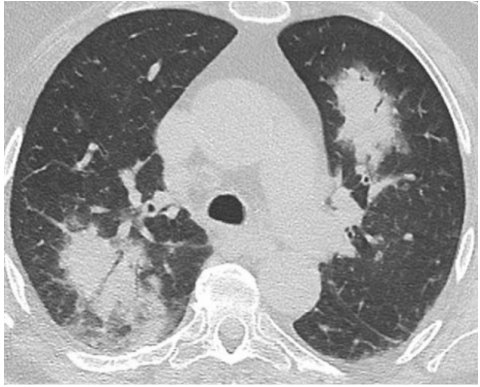

实变是OP病例中最常见的发现,发生于近75%的病例中,病变通常在双基底、支气管血管周围和/或外周。图1A为一名女性患者,右肺上叶周围实变,其曾因乳腺癌接受过放射治疗,并经活检证实为OP。图1B患者左肺下叶和舌叶周围实变,活检证实为继发于淋巴瘤化疗的OP。

图源:Chest, 2022, 162(1):156-178.